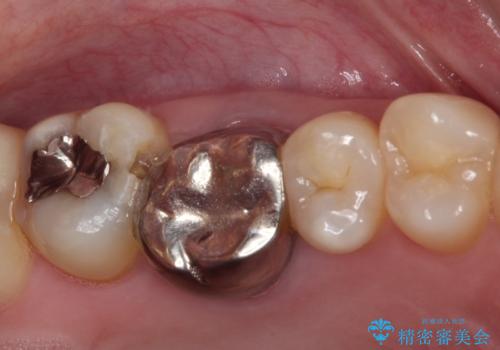

- 奥歯にものが挟まって痛みがあるとのことで来院された患者様です。

目視でも分かるくらいの欠損があり、歯の内部にむし歯が進行している状態でした。

上顎奥歯で目立たないことから、ゴールドインレー(PGAインレー)による修復治療をおこなうこととしました。